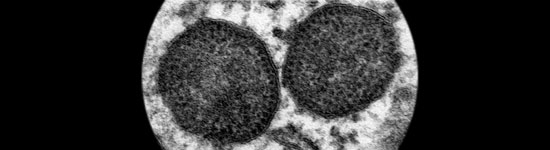

La infección experimental por Mhyo y PCV2 ha proporcionado resultados un tanto divergentes.

El PCV2 se ha ido asociando cada vez a más patologías, denominadas colectivamente enfermedades asociadas a PCV2 (PCVDs), como ES-PCV2, EP-PCV2, EE-PCV2, ER-PCV2, IS-PCV2 y SDNP.